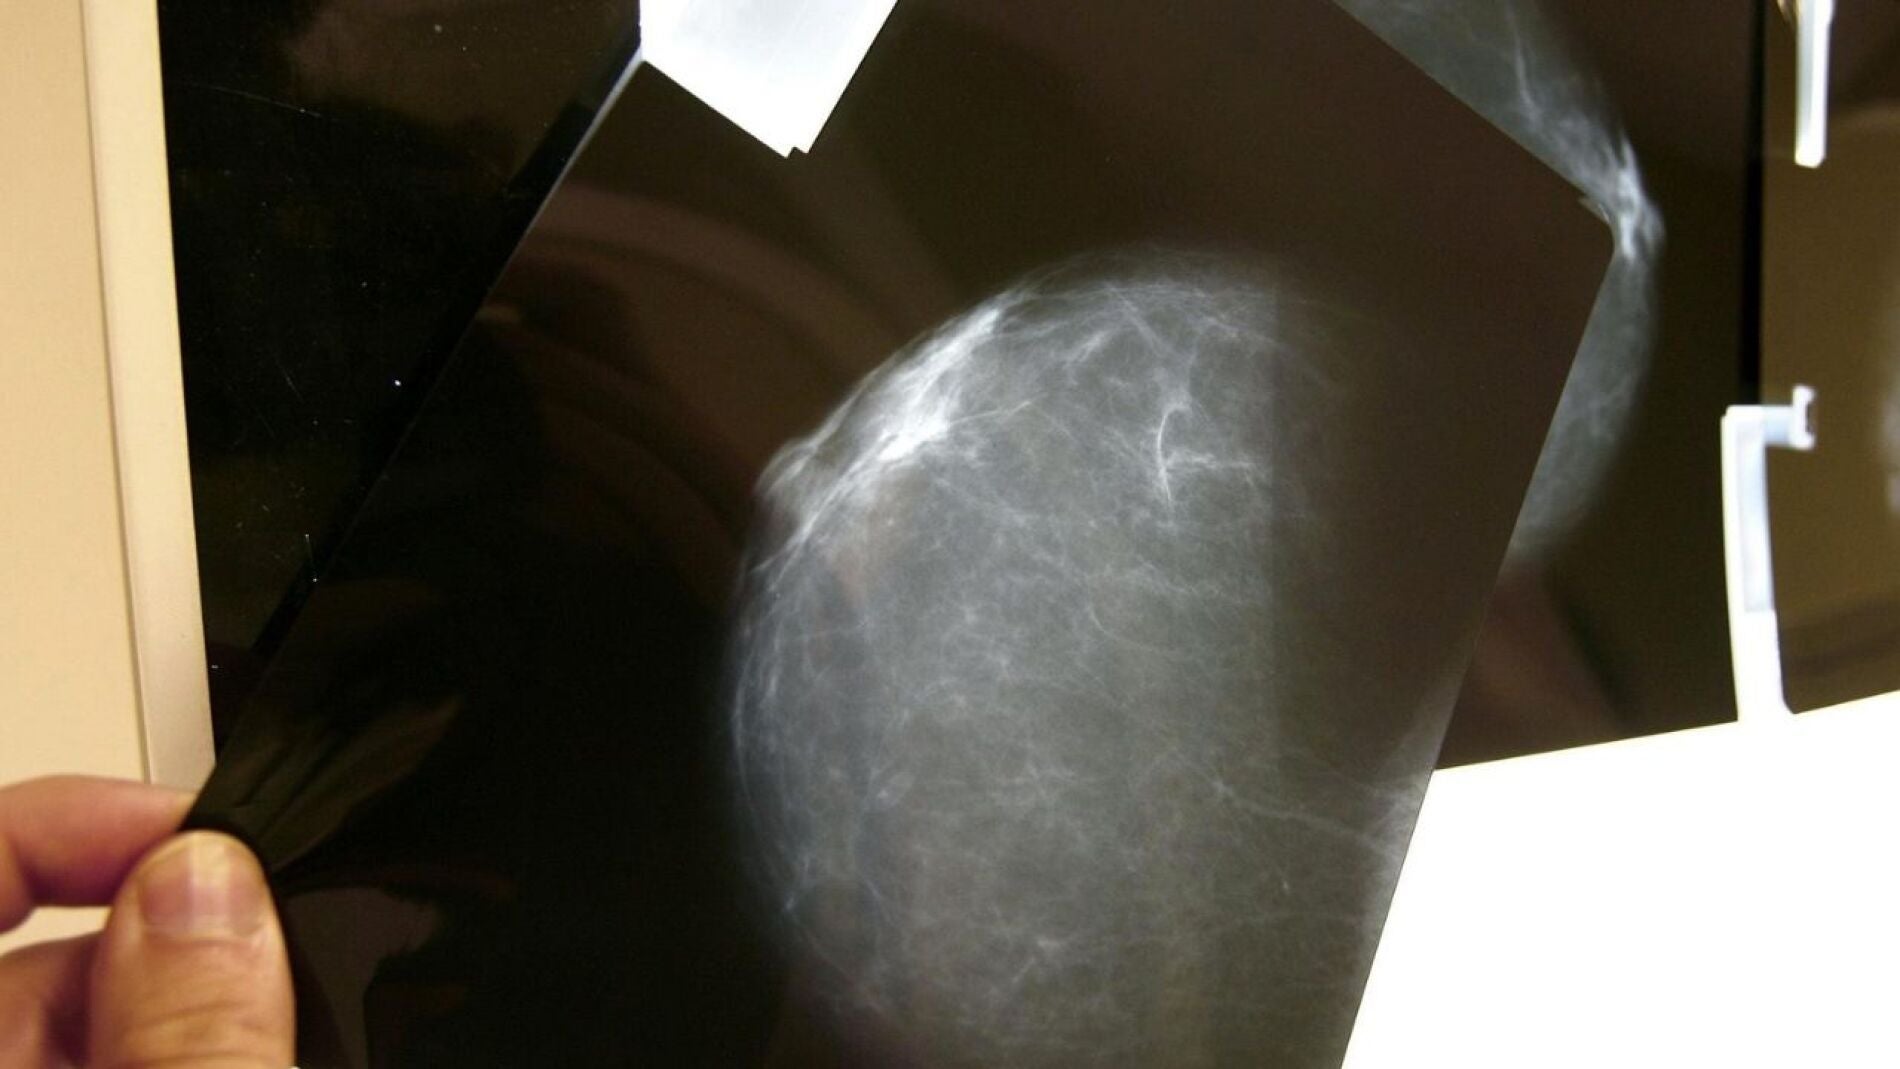

Según un artículo publicado en la revista médica 'Elsevier', escrito por Mercè Marzo-Castillejoa, del Institut Català de la Salut (ICS) y por Carolina Guiriguet Capdevilab y Ermengol Coma Redonb, ambos de los Sistemas de Información de los Servicios de Atención Primaria (SISAP) y del Institut Català de la Salut, "durante los primeros meses de la pandemia "se aplazaron los programas de prevención primaria (deshabituación tabaco, vacuna del virus papiloma humano) y también se pospusieron los cribados (mama, colorrectal y cérvix), lo cual ha ocasionado un descenso de la detección de cánceres asintomáticos". Indican que la telemedicina ha afectado directamente en esta evaluación de los signos y síntomas.